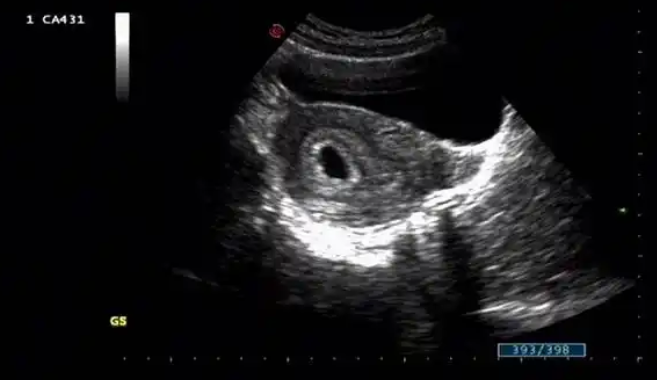

早孕双环征是一种妊娠期间出现的妇科疾病,对孕妇和胎儿的健康都存在一定的风险。本文将从以下三个方面详细介绍早孕双环征的好与坏。

首先,早孕双环征的出现表明孕妇体内的黄体功能正常。黄体在孕妇体内产生的黄体酮可以维持胎儿的着床,并促使胚胎的发育。早孕双环征的存在可以让孕妇和家人更加放心,证明孕妇的黄体功能正常,预示着妊娠有较高的成功率。